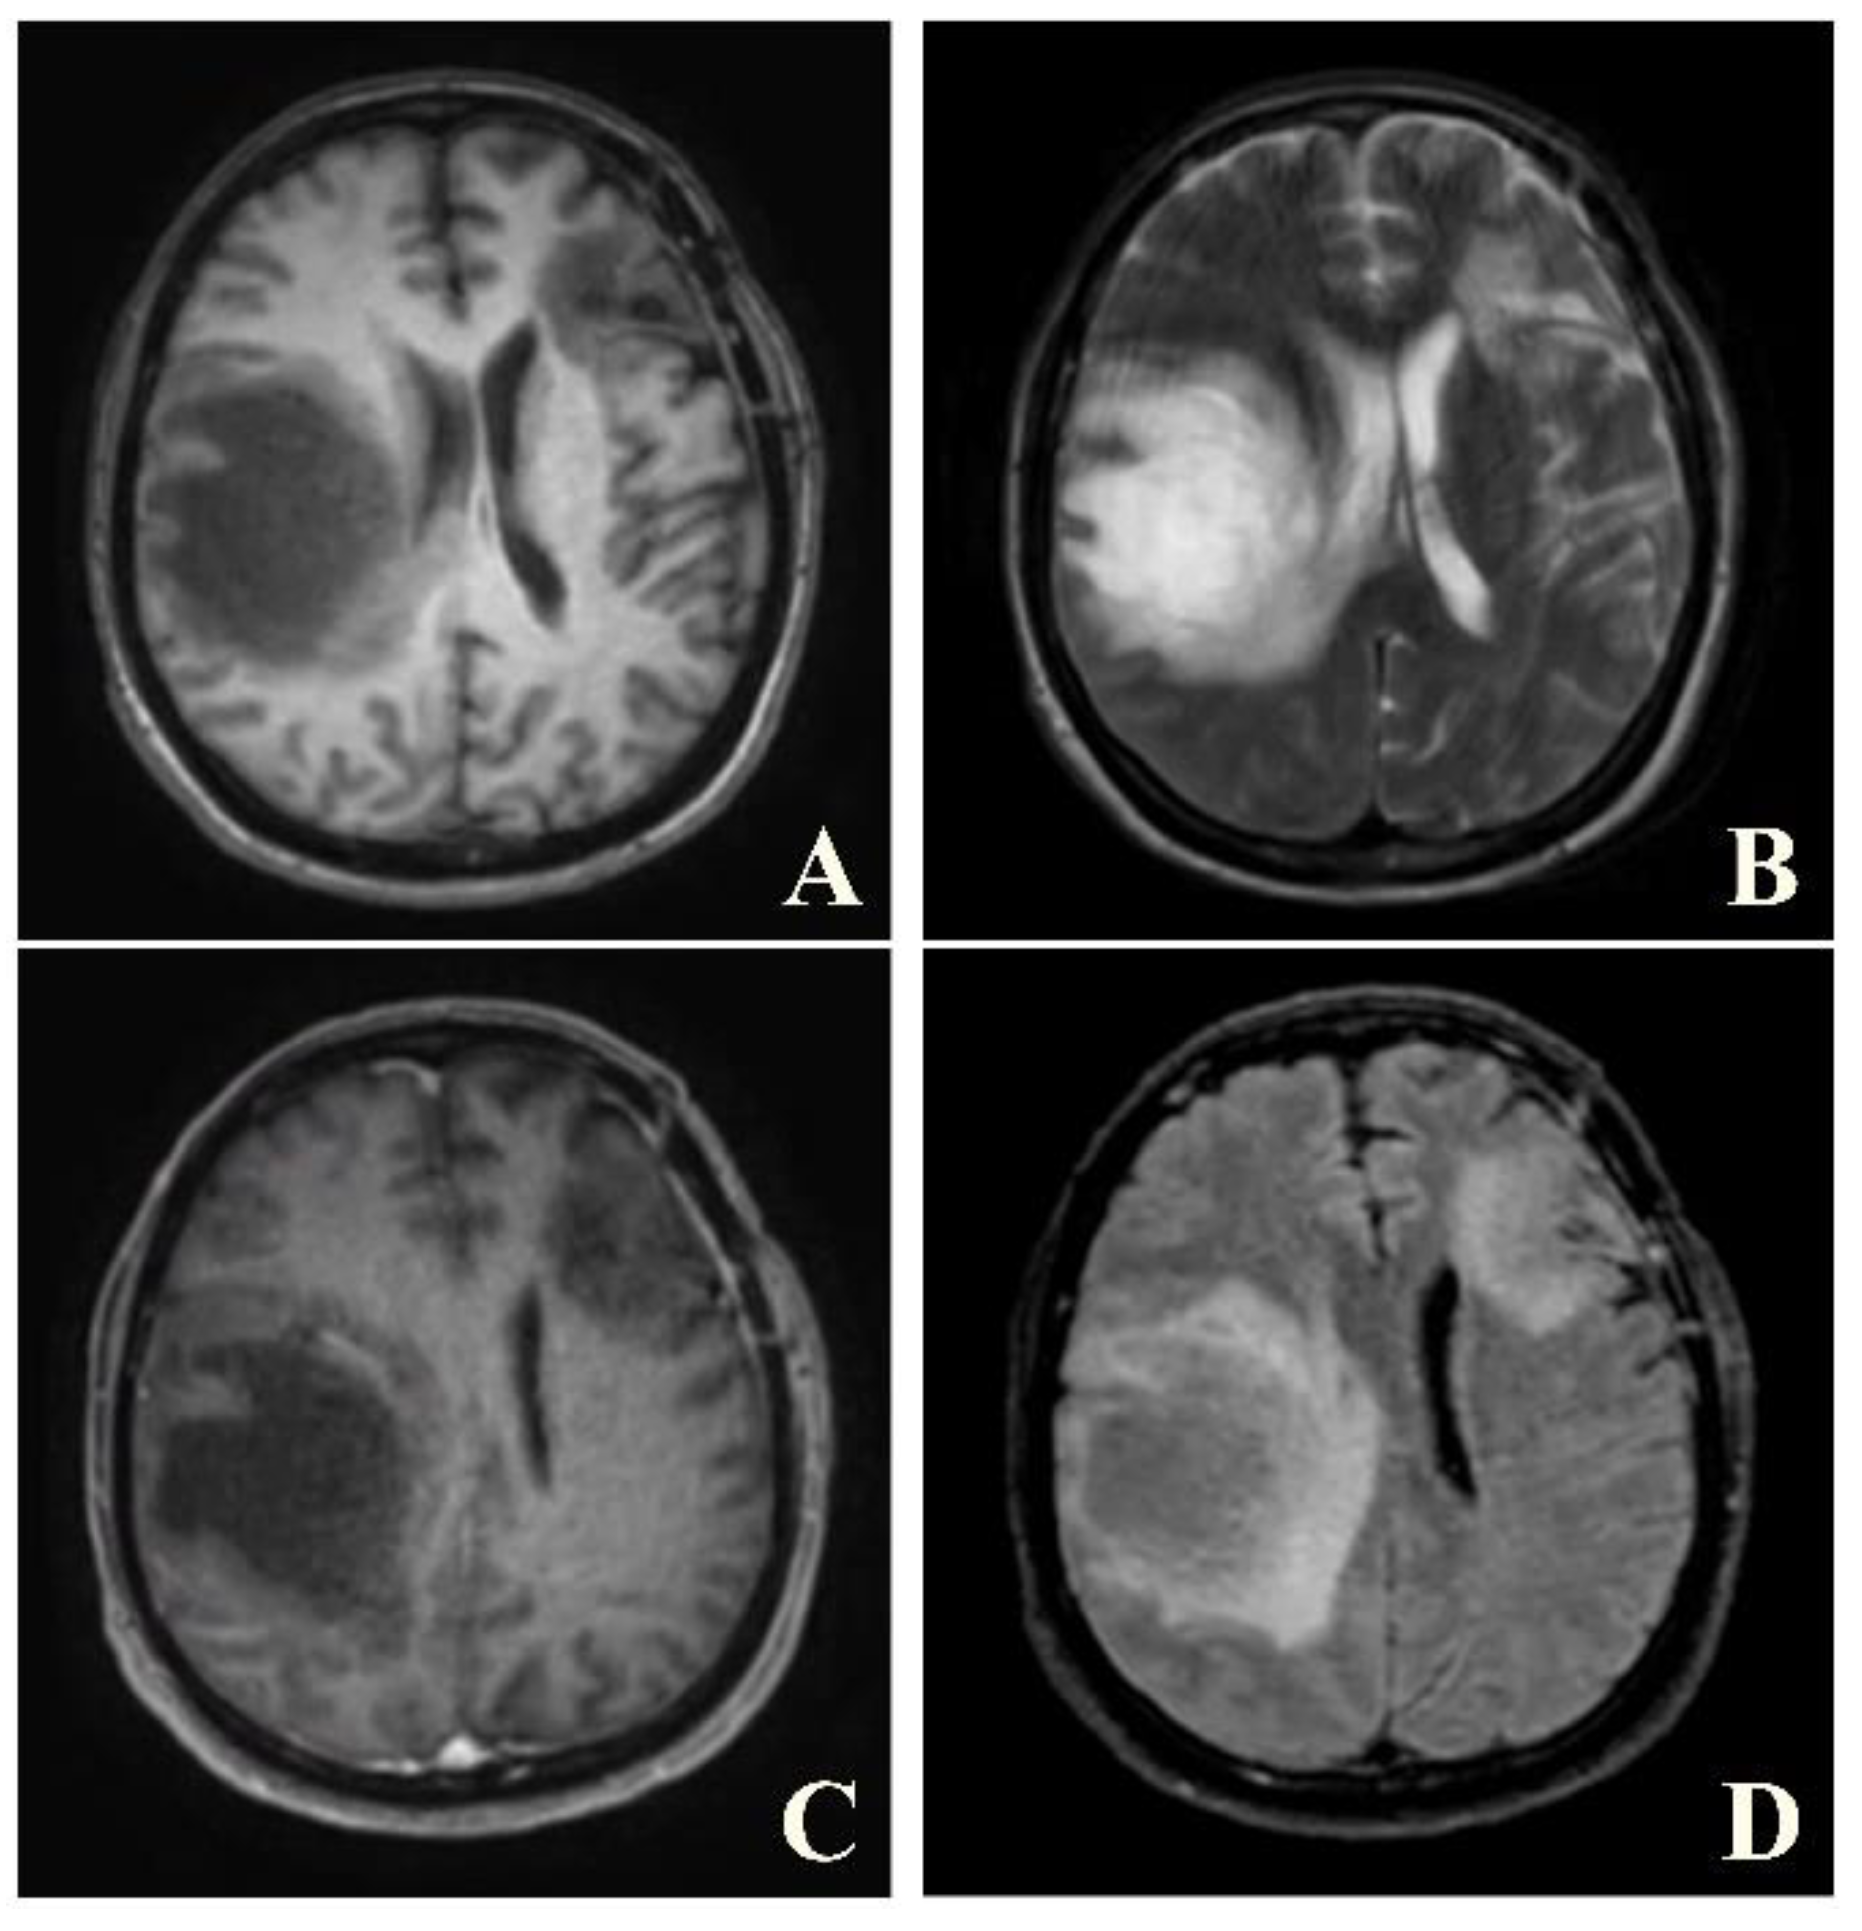

Figure 2. Axial T1W (A), T2W (B), post-contrast T1W (C) and post-contrast FLAIR (D) images of the same patient reveal tumor-like lesion with surrounding vasogenic edema at left frontal and right parietal lobes. The patient was suspected to have high-grade glioma and underwent biopsy. Pathological result was consisted with demyelination, yielding a final diagnosis of tumefactive MS. The patient was given treatment with high-dose steroids.

A brain MRI was available for all 32 patients, all of whom showed abnormalities. Most of the patients (19, 59.4%) were subjected to MRI soon after clinical presentation and during follow-up. The lesions were most commonly identified in the periventricular regions (78.1%), juxtacortical regions (75%) and deep white matter (62.5%). Cortical lesions were identified in only eight patients (25%). Other locations included in the McDonald criteria (2017) were the brainstem and cerebellum, which were found in 59.4 and 21.9% of all patients, respectively. The most common characteristic of the lesions was a round/oval discrete appearance (29 patients, 90.6%). A T1W-blackhole and classic Dawson’s finger (Figure 1) were equally identified in 20 patients (62.5%). A tumefactive form was found in two patients (Figure 2 and Figure 3). There were also two patients with target-like lesions, resembling Balo’s concentric sclerosis (Figure 4). The maximal diameter of the lesions was most commonly less than 13 mm (34.4%). A few patients showed lesions measuring more than 52 mm (9.4%), particularly those with confluent lesions. The total number of lesions in the T2W images was most commonly counted at less than 23 (50.0%), while there were up to four patients with extensive lesions, or more than 47 (12.5%) (Figure 5). Gadolinium-enhancing lesions were identified in nine patients (28.1%), who mostly only had one or two of these lesions (in five out of nine patients). Of these, the most common enhancing pattern was nodular enhancement (in four patients). The classic incomplete ring enhancement was identified in two patients, while complete ring enhancement was found in one patient. A visual assessment of the brain volume found brain atrophy in four patients (12.5%). Two patients with tumefactive MS showed brain swelling (Table 2).